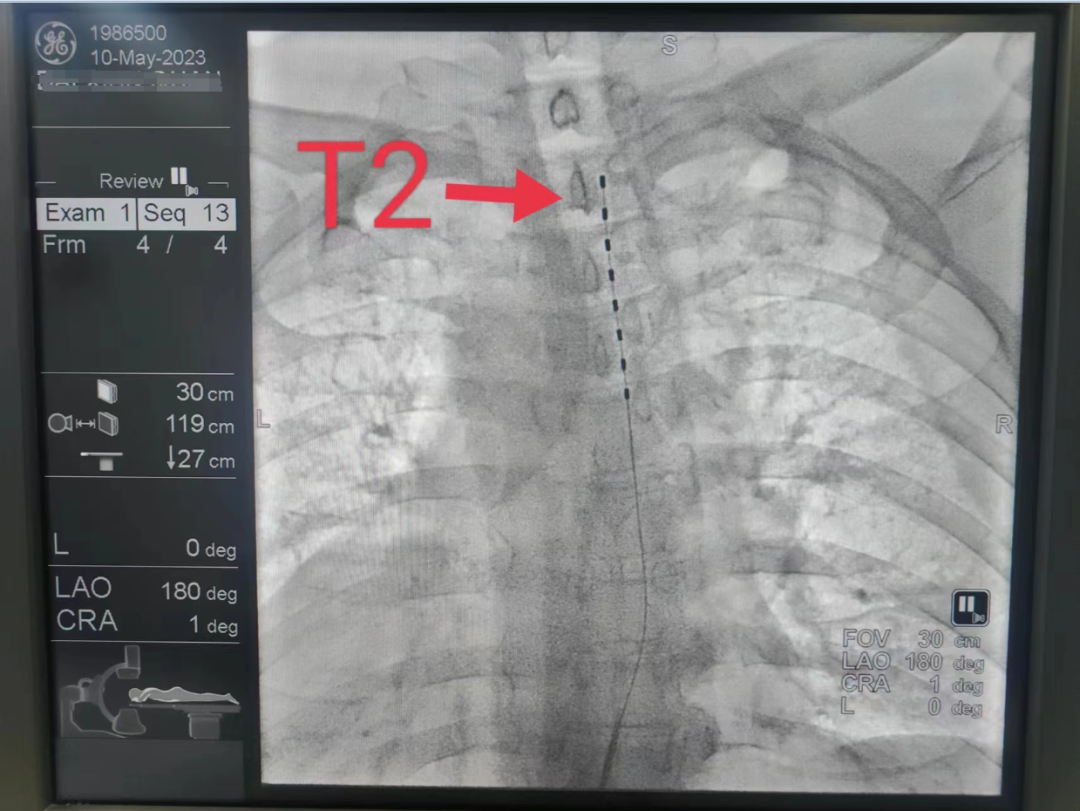

5月10日,在西南医科大学疼痛科团队指导下,我院疼痛科顺利为1位带状疱疹后神经痛患者完成脊髓电刺激置入术,让该患者从每日饱受剧痛折磨的噩梦中彻底解放。

带状疱疹后遗神经痛是常见的神经病理性疼痛,也是治疗效果极差的一类疼痛性疾病,该技术的开展,让更多的PHN患者看到了新的希望。

脊髓电刺激是将脊髓刺激电极置于椎管的硬膜外腔后间隙,刺激电极产生电场,通过电流刺激脊髓后柱的传导束和后角感觉神经元,阻断/干扰疼痛信号通过脊髓向大脑传递,从而达到治疗疼痛或其它疾病目的的一种治疗方法。具有安全、微创、可逆、可调的特点。脊髓电刺激的有效率是综合药物治疗的5倍,可以有效改善疼痛,提高患者生活质量。